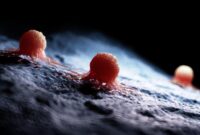

Para ilmuwan telah menciptakan jenis baru antibodi super-kuat yang secara signifikan dapat meningkatkan imunoterapi kanker. Dalam kemajuan yang menarik untuk pengobatan kanker, para ilmuwan…

Sebuah studi yang dipimpin oleh UC San Diego yang menghubungkan paparan anak usia dini dengan bakteri toksin colibactin dengan peningkatan kanker kolorektal awal, menemukan…